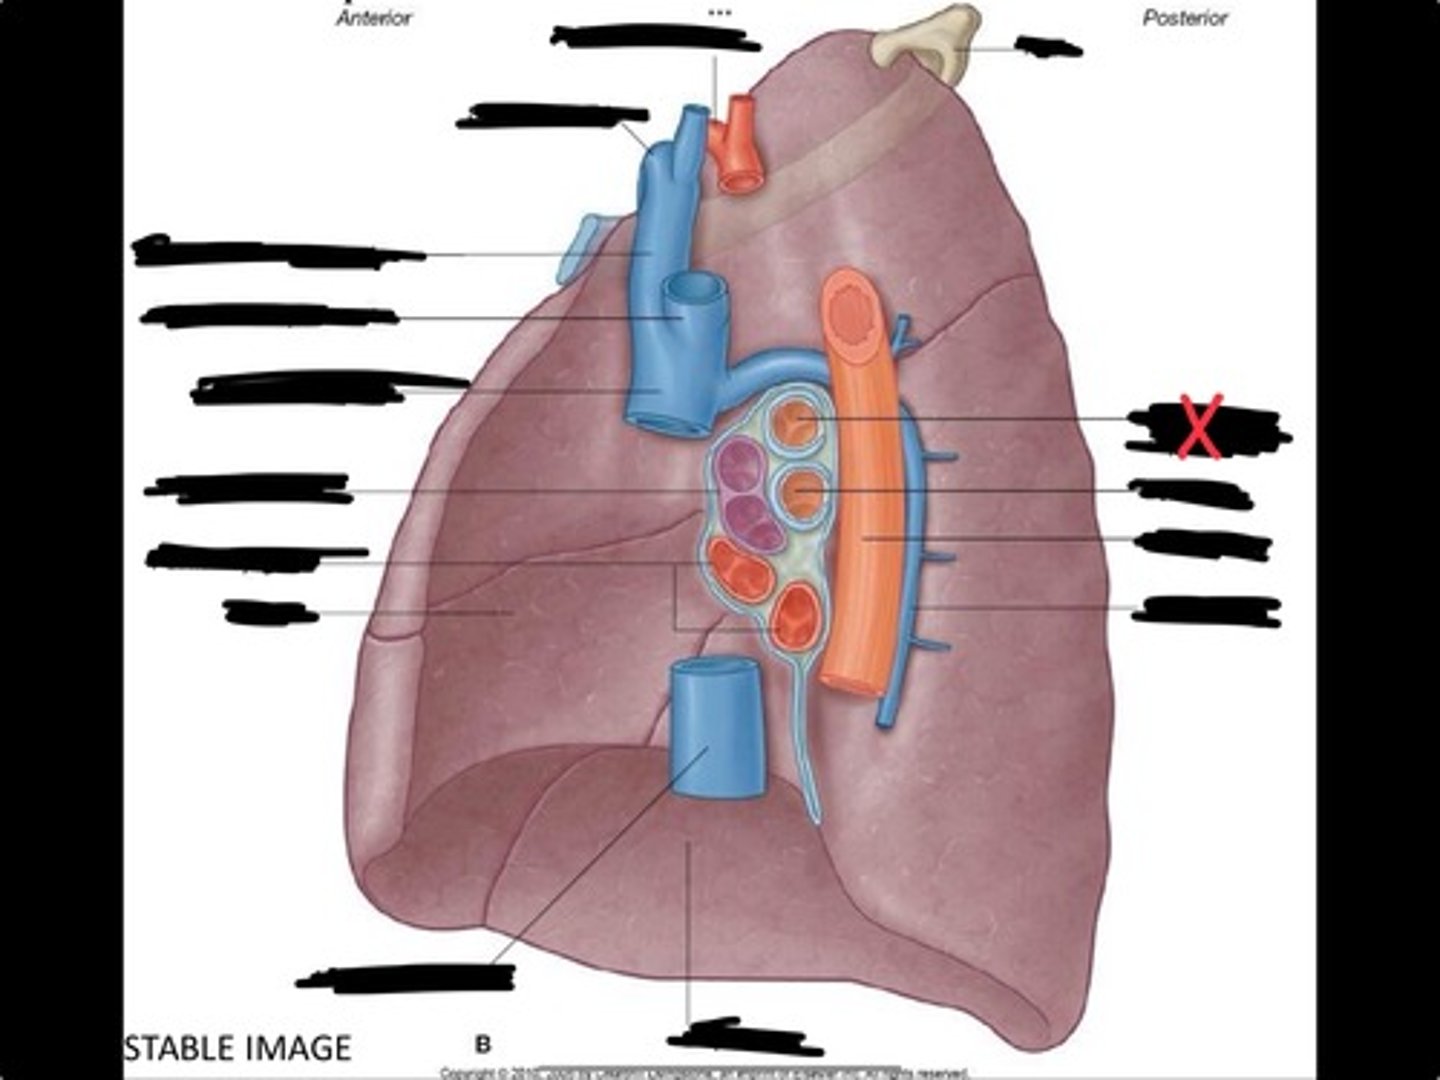

Lung

Pleural cavity

Visceral pleura

Parietal cavity

Esophagus

Bronchus

Pulmonary artery

Pulmonary vein

Pulmonary artery

Bronchus to superior lobe

Pulmonary veins